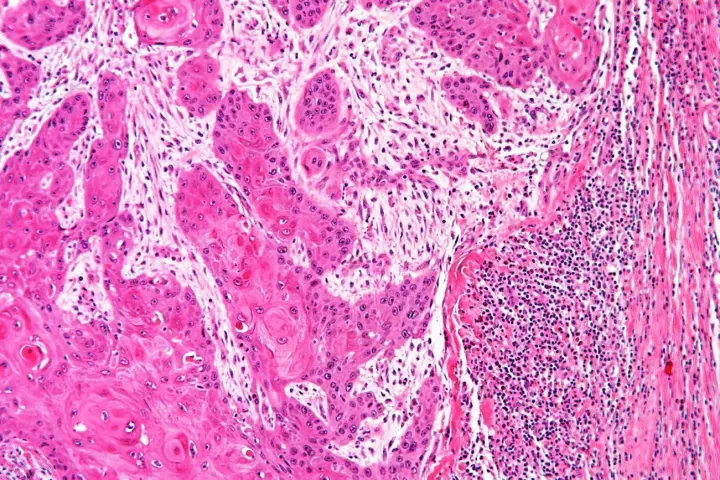

One trick cancer cells use to evade an attack by the body's immune system is to shield themselves behind a particular type of healthy cell, but scientists at the University of Southampton have now found a new way to intervene in this process.